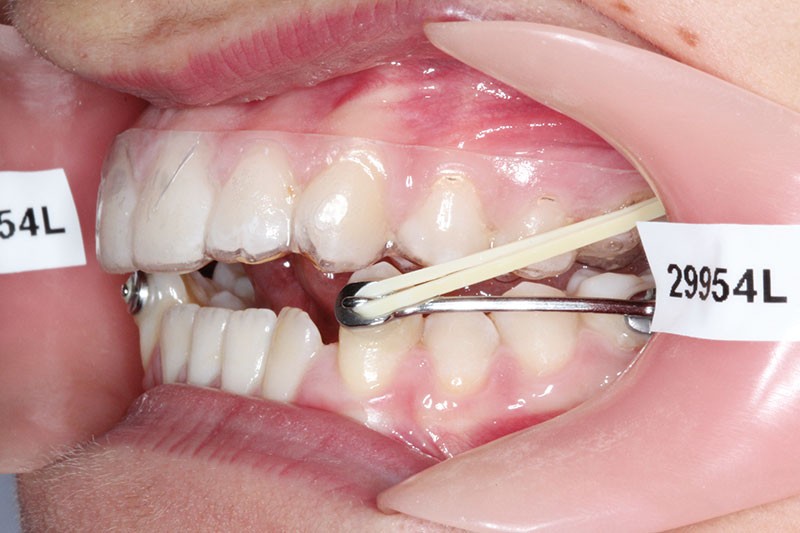

1re phase : recul des secteurs latéraux mandibulaires avec le Motion Classe III Carriere (fig. 4 à 6)

Nous mettons en place des bras latéraux Motion associés à des élastiques intermaxillaires ancrés sur des brackets sur 17 et 27 et une gouttière thermoformée maxillaire portée jour et nuit :

• 1er mois : élastiques 6 oz. 1/4”

• 2e mois et suivants : élastiques 6 oz.1/4“

L’objectif de cette étape est d’obtenir un recul des secteurs latéraux mandibulaires afin de positionner les molaires et canines en classe I et de réorienter le plan d’occlusion en haut en avant.